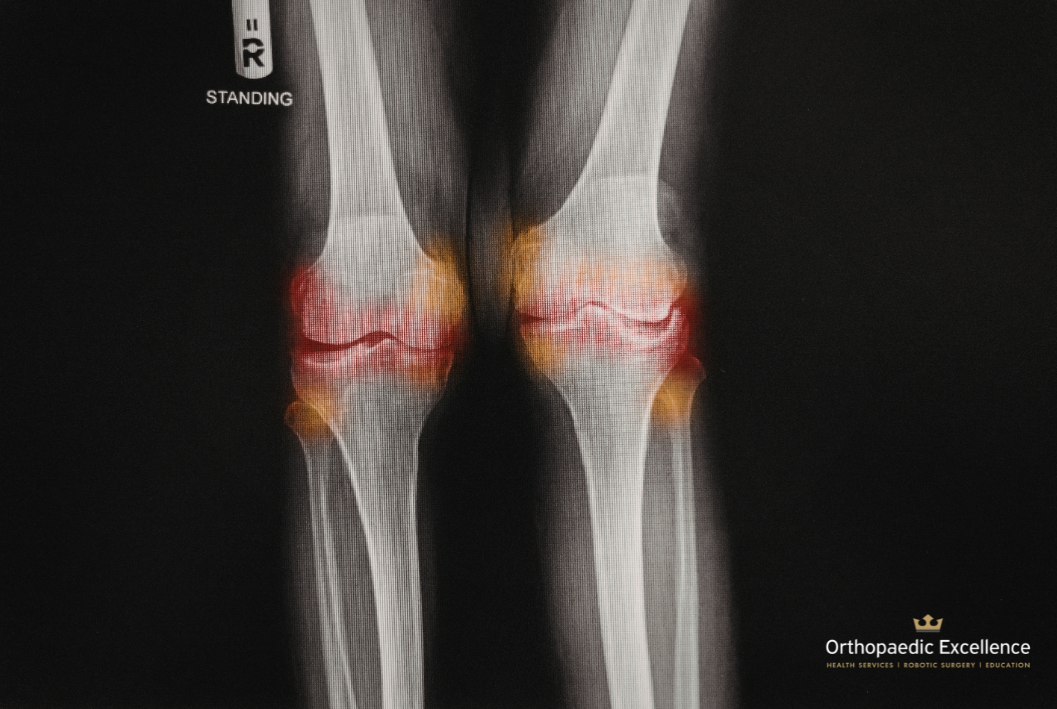

Ακτινογραφίες και χαρακτηριστικά ευρήματα

Επιπλέον, οι ακτινογραφίες αποτελούν το σημαντικότερο απεικονιστικό εργαλείο για την επιβεβαίωση της διάγνωσης, αν και δεν απαιτούνται πάντα. Τα χαρακτηριστικά ακτινολογικά ευρήματα περιλαμβάνουν:

• Στένωση του μεσάρθριου διαστήματος (μειωμένος χώρος μεταξύ των οστών)

• Παρουσία οστεοφύτων (οστικές προεξοχές) στα όρια της άρθρωσης

• Σκλήρυνση του υποχόνδριου οστού

• Υποχόνδριες κύστεις

Ωστόσο, ένα κρίσιμο στοιχείο που συχνά παραβλέπεται είναι ότι τα ακτινολογικά ευρήματα δεν συμβαδίζουν πάντα με την κλινική εικόνα. Στην πράξη, εμφανίζονται συχνά ασθενείς με έντονο πόνο αλλά σχετικά μικρή βλάβη στις αρθρώσεις, ενώ άλλοι με σημαντική ακτινολογική φθορά αναφέρουν ελάχιστα συμπτώματα. Το σύστημα σταδιοποίησης Kellgren-Lawrence, από το στάδιο 0 (φυσιολογικό) έως το στάδιο 4 (πλήρης εξάλειψη του μεσάρθριου διαστήματος), χρησιμοποιείται συχνά για την ταξινόμηση της σοβαρότητας.